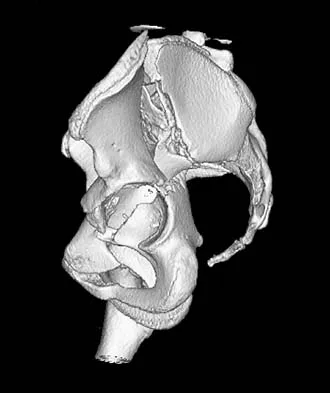

A 21-year-old patient has had pain and a marked decrease in active and passive shoulder motion after having had a seizure 2 months ago as the result of alcohol abuse. Current AP and axillary radiographs and a CT scan are shown in Figures 26a through 26c. Management should consist of

Explanation